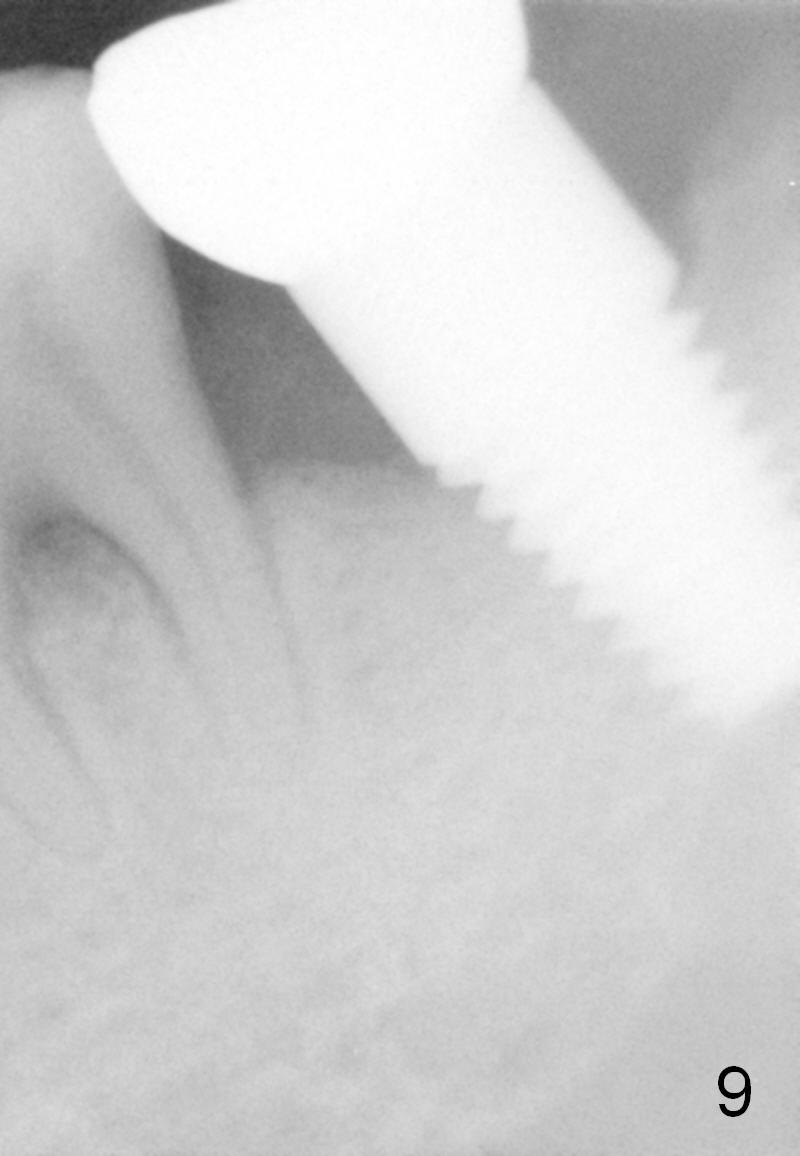

There is no bone resorption 6 months post cementation (12 months postop, Fig.8,9).  Mild bone resorption is observed 3 years post cementation (Fig.10).  It may be related to the large implant (7 mm) in association with chronic periodontitis and bruxism.   The roots of the teeth #19 and 30 fracture 6 years 5 months post cementation at #18 (Fig.11).  Since gingival recession is severe at #18 probably related to the large implant, the one at #19 will be designed small.